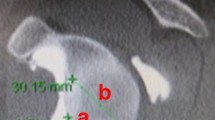

A clinical image viewing software capable of 3D reconstruction (IDS7 Workstation Version 22.2; Sectra) was used to classify CT images according to the previously described 3D classification for DAS [15]. First, the scapular plane was reconstructed in 3D using two-dimensional orthogonal planes (axial, coronal, and sagittal): The glenoid center, trigonum and inferior angle of the scapula were aligned in one plane (Fig. 1). Following this, anteroposterior alignment was classified as posterior, centered or anterior; superoinferior alignment was classified as superior, centered or inferior and combined with an erosion grade (1–3) (Fig. 2) [15]. Subluxation of the humeral head center from the scapular axis (line passing from trigonum scapulae through glenoid center) was assessed relative to the radius of the humeral head (Fig. 3):

Method for determining the percentage of subluxation, s, of the humeral head center from the scapular axis, ax, relative to the radius of the humeral head, r [15]

Centered alignment was defined as: Between 20% posterior and 5% anterior subluxation in the anteroposterior direction; between 5% inferior and 20% superior subluxation in the superoinferior direction, as previously described [15]. Additionally, alignment could be described as extra-posterior if posterior subluxation was > 60% of the humeral head radius (> 80% of the diameter), or extra-superior if static acetabularization was present [15]. Where alignment seemed to be obvious, observers were not required to perform measurements. In borderline cases the scapula axis, humeral circumference with center point, radius and subluxation of the center of the humeral head from the scapula axis was determined to quantify the classification (Fig. 4).

Method for measurement of humeroscapular alignment on A coronal plane and B and C cross–sectional plane computed tomography scans, after reconstruction of the scapular plane in three dimensions. (B) The center of rotation of the humeral head is determined at the widest cross–section of the head and (C) is then translated down to the level of the scapular axis for measurement of subluxation. (D) When higher–grade erosion with partial humeral head collapse and osteophytes are present, measurement is more challenging. Osteophytes (red arrow), whether on the humeral or glenoid side, are disregarded. The center of rotation is determined using the intact outer margins of the humeral joint surface (blue stars) as landmarks [15]